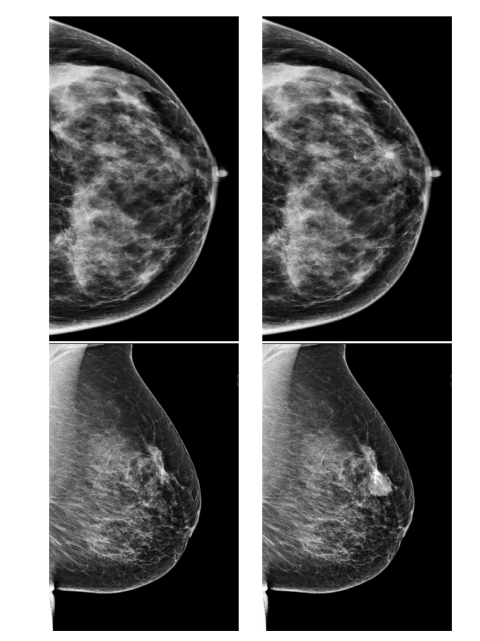

Fig. 9. Two examples of synthetic cases comparing the original healthy control image(left) and the result of the synthetic lesion insertion (right). The network was trainedon both the original healthy control and the synthetic lesions

图9. 两个合成病例的示例,比较了原始的健康对照图像(左)与合成病灶插入后的结果(右)。网络同时在原始健康对照图像和合成病灶上进行了训练。